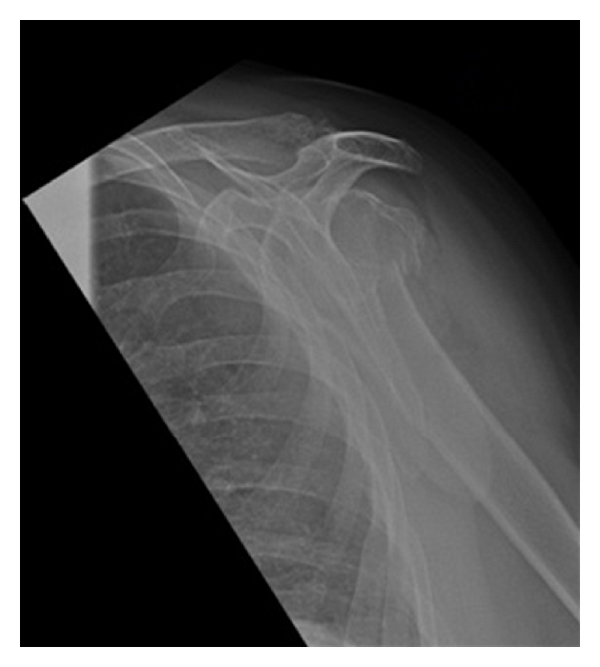

Her arm was immobilised in a collar and cuff and it was decided to manage her conservatively with routine initial weekly follow-up in outpatients. At two weeks, her fracture was displaced further but given her pain-free range of movement it was decided to continue conservative management. She was seen regularly over a number of weeks in the fracture clinic with a satisfactory comfortable range of movement and an adequately reduced fracture radiographically. At 4 months, however, she presented with a very painful shoulder which she could hardly move. Radiographs confirmed nonunion and it was decided to proceed with a reverse-geometry shoulder replacement under general anaesthesia supplemented with an interscalene block (ISB) (Figure 2).

(a)

(b)

(c)